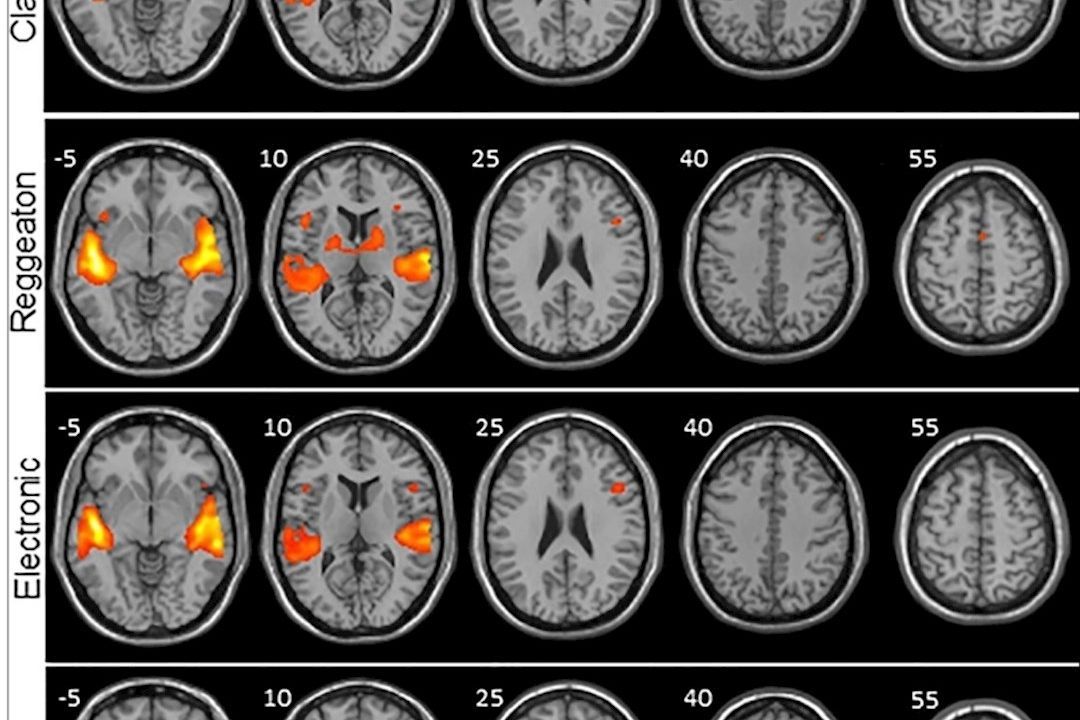

Frente a la música clásica, el folclore y la electrónica, el reguetón provoca una mayor activación en las regiones del cerebro encargadas de procesar no sólo los sonidos, sino también el movimiento, según un estudio llevado a cabo por investigadores canarios sobre la actividad cerebral que produce escuchar diferentes estilos musicales.El estudio forma parte de la tesis doctoral del neurocirujano del Hospital Universitario Nuestra Señora de la Candelaria en Santa Cruz de Tenerife Jesús Martín-Fernández, quien ha trabajado en la investigación junto a los neurocientíficos Iballa Burunat, Cristián Modroño, José Luis González-Mora y Julio Plata-Bellod.

Los investigadores analizaron por un lado anatómicamente el cerebro de cada participante y luego la señal BOLD, que consiste en ver qué áreas del cerebro reclutan oxígeno (que es lo que sucede cuando se activan) y a través de un software se representaron con diferentes colores según se activasen más o menos.La razón por la que se eliminó la letra de los clips musicales de cada estilo es "porque pretendíamos estudiar de la forma más pura posible el procesamiento de la música, y el lenguaje podría (al emplear otras vías neurales) mostrarnos activación cerebral que no es específica de la música".

Y fue el reguetón el que mostró mayor activación en las regiones del cerebro encargadas de procesar los sonidos (áreas auditivas) y de procesar el movimiento (áreas motoras), unas diferencias que resultaron mayores cuando se comparaban con la música clásica.La electrónica también mostró una mayor activación de las regiones motoras, pero significativamente menor en comparación con el reguetón "y lo que más nos llamó la atención fue la activación de una región primitiva del cerebro: los ganglios basales".

La mayor activación provocada por el reguetón implica que hay más regiones cerebrales auditivas y motoras que se activan y por lo tanto hay una mayor maquinaria trabajando en procesar la música.La activación tan significativa en las áreas del cerebro encargadas del movimiento podría deberse "a la generación de un pulso interno dentro de nosotros al tratar de adivinar cuándo viene el siguiente pulso. Es como si el reguetón, con ese ritmo peculiar y repetitivo nos preparara para el movimiento, para bailar sólo con escucharlo".